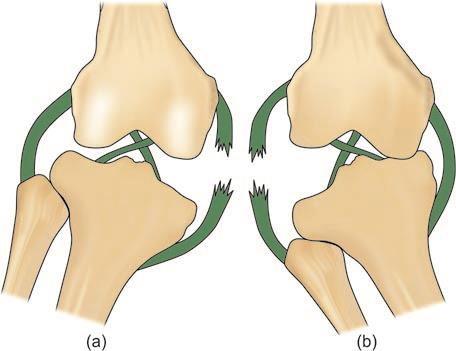

Anterior and posterior cruciate ligaments: Prevent anterior and posterior displacement of the tibia.

Injuries: Meniscal tears, cruciate ligament ruptures, collateral ligament injuries.